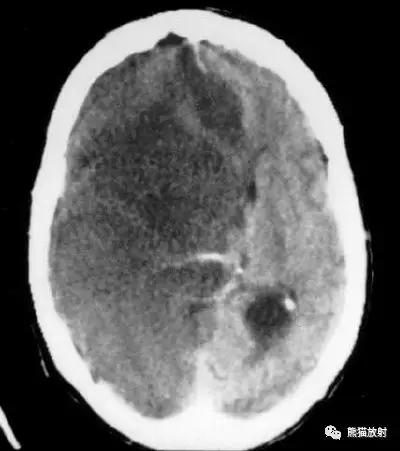

左侧大脑中动脉血栓形成(箭头)—— “大脑中动脉高密度征”,发病后不久行CT检查:相应的血管区域见缺血性病变。

右侧豆状核梗死灶(发病后15d),明显均匀强化。另左侧丘脑见腔隙性梗死灶。

左侧大脑中动脉区域大面积梗死,明显不均质强化。